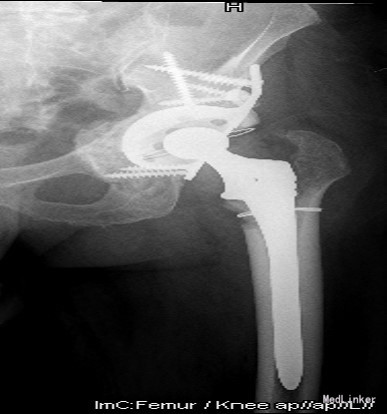

诊断:1.左侧THA术后假体松动、聚乙烯内衬磨损、炎性假瘤形成 2.左侧THA术后髋臼及股骨近端骨溶解 3.左侧THA术后髋臼及股骨近端骨缺损(髋臼AAOS III型 股骨Paprosky II型) 4.右髋重度骨关节炎 5.高血压 (2期 高危) 治疗:完善检查,调整患者全身条件后在全麻下行左侧全髋关节假体取出+炎性假瘤切除+异体骨植骨+髋臼重建+人工全髋关节翻修术,术中发现:左髋关节囊后外侧炎性假瘤形成,与关节腔相通,内有大量咖啡色混浊液体,髋臼及股骨近端骨溶解导致骨缺损,以髋臼前壁及下壁和股骨近端严重,小转子消失,关节腔周围大量炎性坏死组织。髋臼假体松动。术中安放左侧Zimmer64mmCage,并用8枚不同长度螺钉固定可靠,Cage内放骨水泥后安放外径59mm,内径28mm聚乙烯内衬并调整前倾及外展角度合适,股骨侧安放12#加长股骨柄,28mm直径、+1.5颈长陶瓷股骨头。